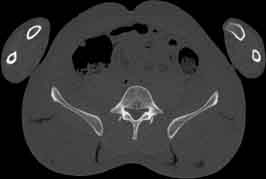

Visible Human male: Sectio transversalis 1751

CT